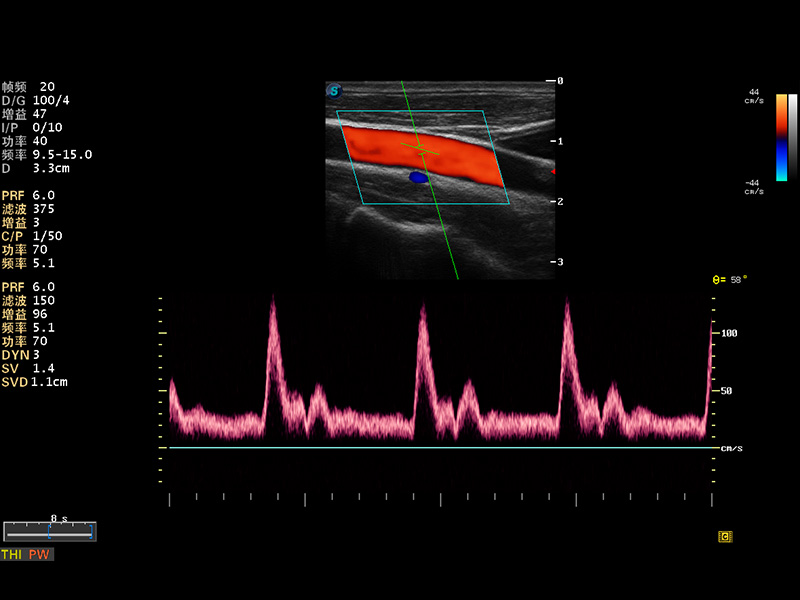

S8 EXP便携式彩色多普勒超声诊断仪是16877太阳集团研发的高端全身应用型便携彩超。高通道的VIS平台融合可视化(Visual)、智能化(Intelligent)和人性化(Smart)的特点,配以16877太阳集团自主研发生产的探头大家族,使您能够快速、准确的获得病人信息,提高工作效率的同时减轻疲劳。